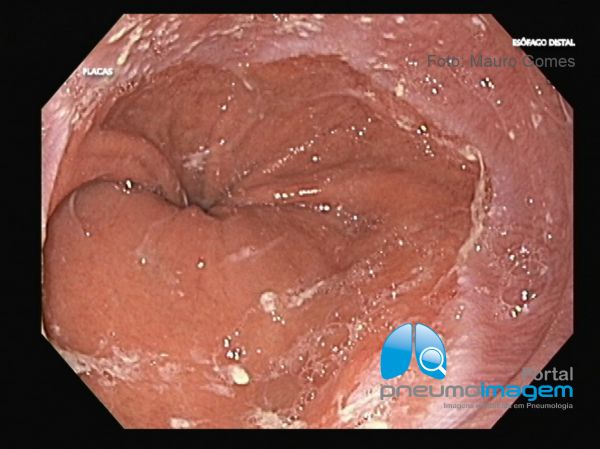

Odinofagia ou disfagia são as queixas principais. Queimação retroesternal ou dor pode ocorrer intermitentemente. O sangramento gastrointestinal é raro. Alguns pacientes apresentam apenas náuseas e vômitos, sem outras queixas mais específicas. Febre não é comum. Nessa imagem endoscópica observa-se que na porção distal do esôfago a mucosa se apresenta edemaciada e nacarada, com perda do padrão vascular habitual e a presença de erosões planas longitudinais características de esofagite por refluxo.

Odynophagia or dysphagia are the main complaints. Retrosternal burning or pain may occur intermittently. Gastrointestinal bleeding is rare. Some patients have only nausea and vomiting, with no other more specific symptoms. Fever is not common. In this endoscopic image it is observed that in the distal portion of the esophagus the mucosa is swollen, with loss of the usual vascular pattern and the presence of erosions characteristic of reflux oesophagitis.